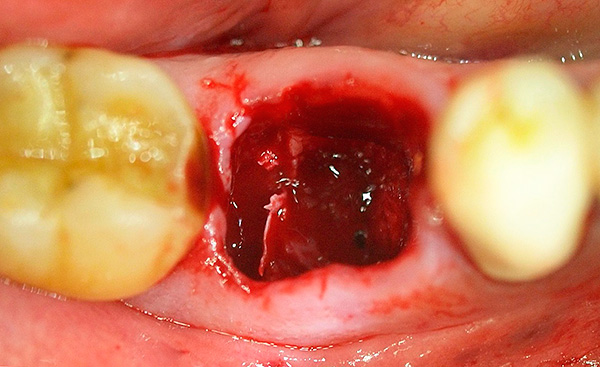

Dopo l'estrazione del dente, un coagulo di sangue riempie la ferita, il che dovrebbe consentire ai fattori di immunità di affrontare le tracce di infezione e innescare il meccanismo di guarigione efficace del foro. Per molti, questo meccanismo è innescato da una cascata di reazioni infiammatorie - di conseguenza, spesso il 2 ° giorno dopo l'estrazione del dente, il dolore, il gonfiore, la febbre e altri sintomi spiacevoli non solo non scompaiono, ma possono anche aumentare leggermente, causando ansia nel paziente.

Nella foto in basso: nuovi fori dopo aver rimosso due denti contemporaneamente: